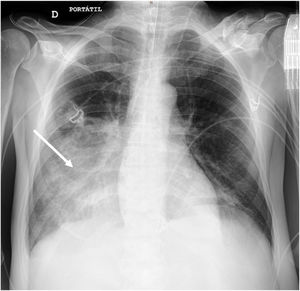

An anteroposterior chest radiography showed an area of lung consolidation in lower right lobe, indicating pneumonia (see Fig. 1). The lung ultrasound showed lobar consolidation, air bronchogram, pleural effusion and fibrin (see Fig. 2), as well as hyperechoic opacities that move centrifugally with respiration (dynamic air bronchogram) (see suppl. material 1). The patient was discharged alive after 2 months.